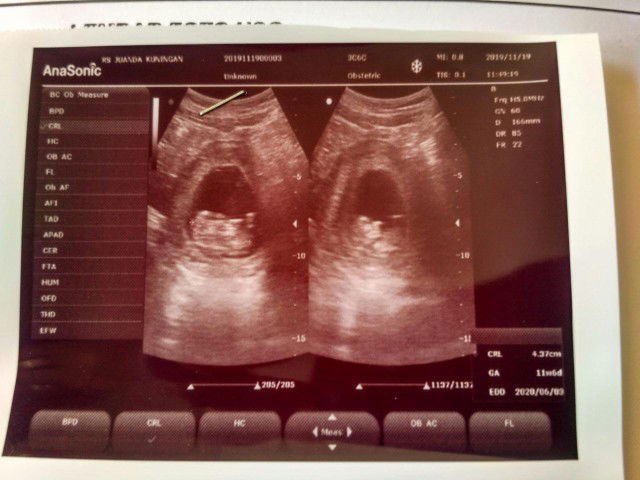

Sudah di usg bun? Takutny itu indikasi plasenta previa